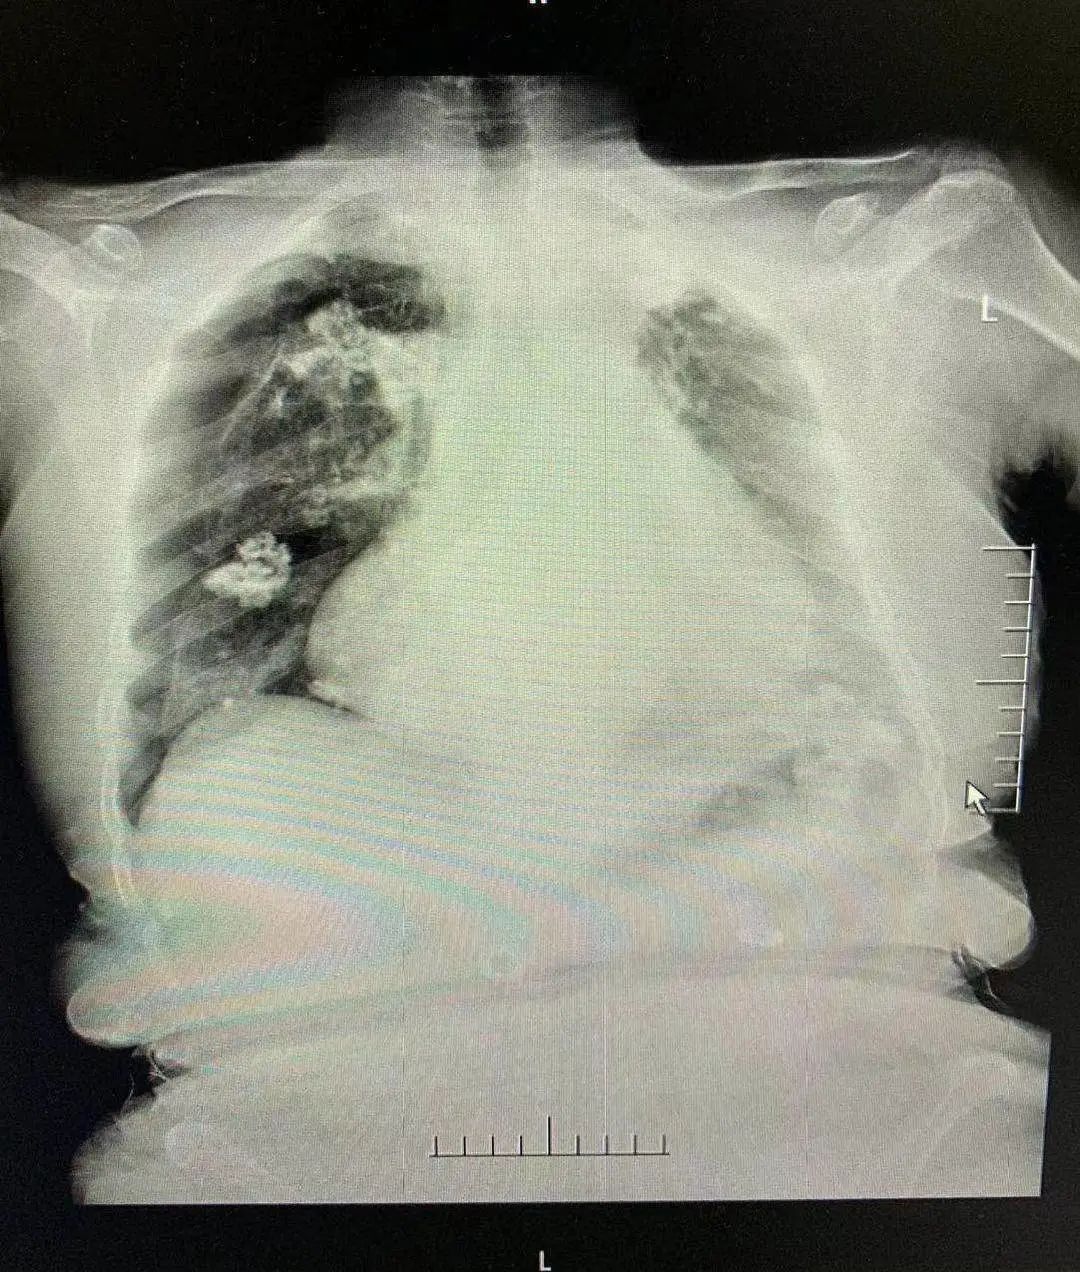

针灸扎穿肺,右肺压缩约50%

陶金医生告诉记者,得知这一情况后,院方立即安排急查床边胸片。最后胸片检查提示:右侧(针灸的一侧)气胸肺压缩50%!也就是说,浦阿姨的右肺被压缩得只剩下一半。一查原因,竟然是针灸不当错扎到肺部所致。

“这是一种‘肺漏气’的现象”,陶金解释,“这种现象的产生,是由于肺部内的气体泄漏到胸腔后,囤积在胸腔又压迫了肺。”而如果漏气得不到缓解,当肺部压缩到最小程度时,浦阿姨面临的将是“呼吸骤停”的威胁。